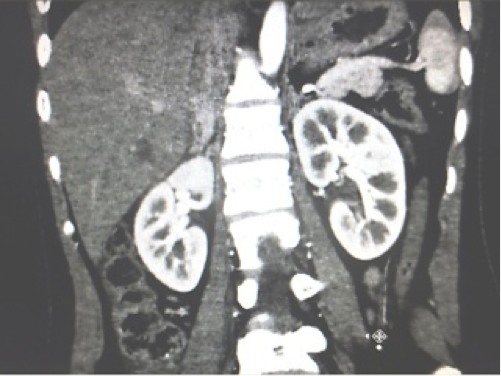

Tại Bệnh viện Từ Dũ, siêu âm và chụp CT tại Trung tâm Medic, phát hiện một thai sống khoảng 22 tuần trong ổ bụng vùng dưới hoành phải (dưới gan phải). Kích thước khối thai là 12x15x17cm. Bánh nhau dày 47mm, xâm lấn gan phải và có mạch máu nuôi xuất phát từ động mạch gan phải. Chẩn đoán: thai dưới gan, chỉ định mổ lấy khối thai và tiên lượng cuộc mổ khó nên mời phẫu thuật viên Bệnh viện Chợ Rẫy kết hợp cùng mổ.

![]() |

Hình 5. Thai nằm dưới gan (ngôi ngược) |

Hình 6. Thai trong ổ bụng. Thai ngôi ngược, có hình ảnh giống như thai trong tử cung nhưng không rõ hình tử cung, khối thai nằm dưới gan nên thấy đầu các xương sườn (Nguồn: ảnh phim Medic) |